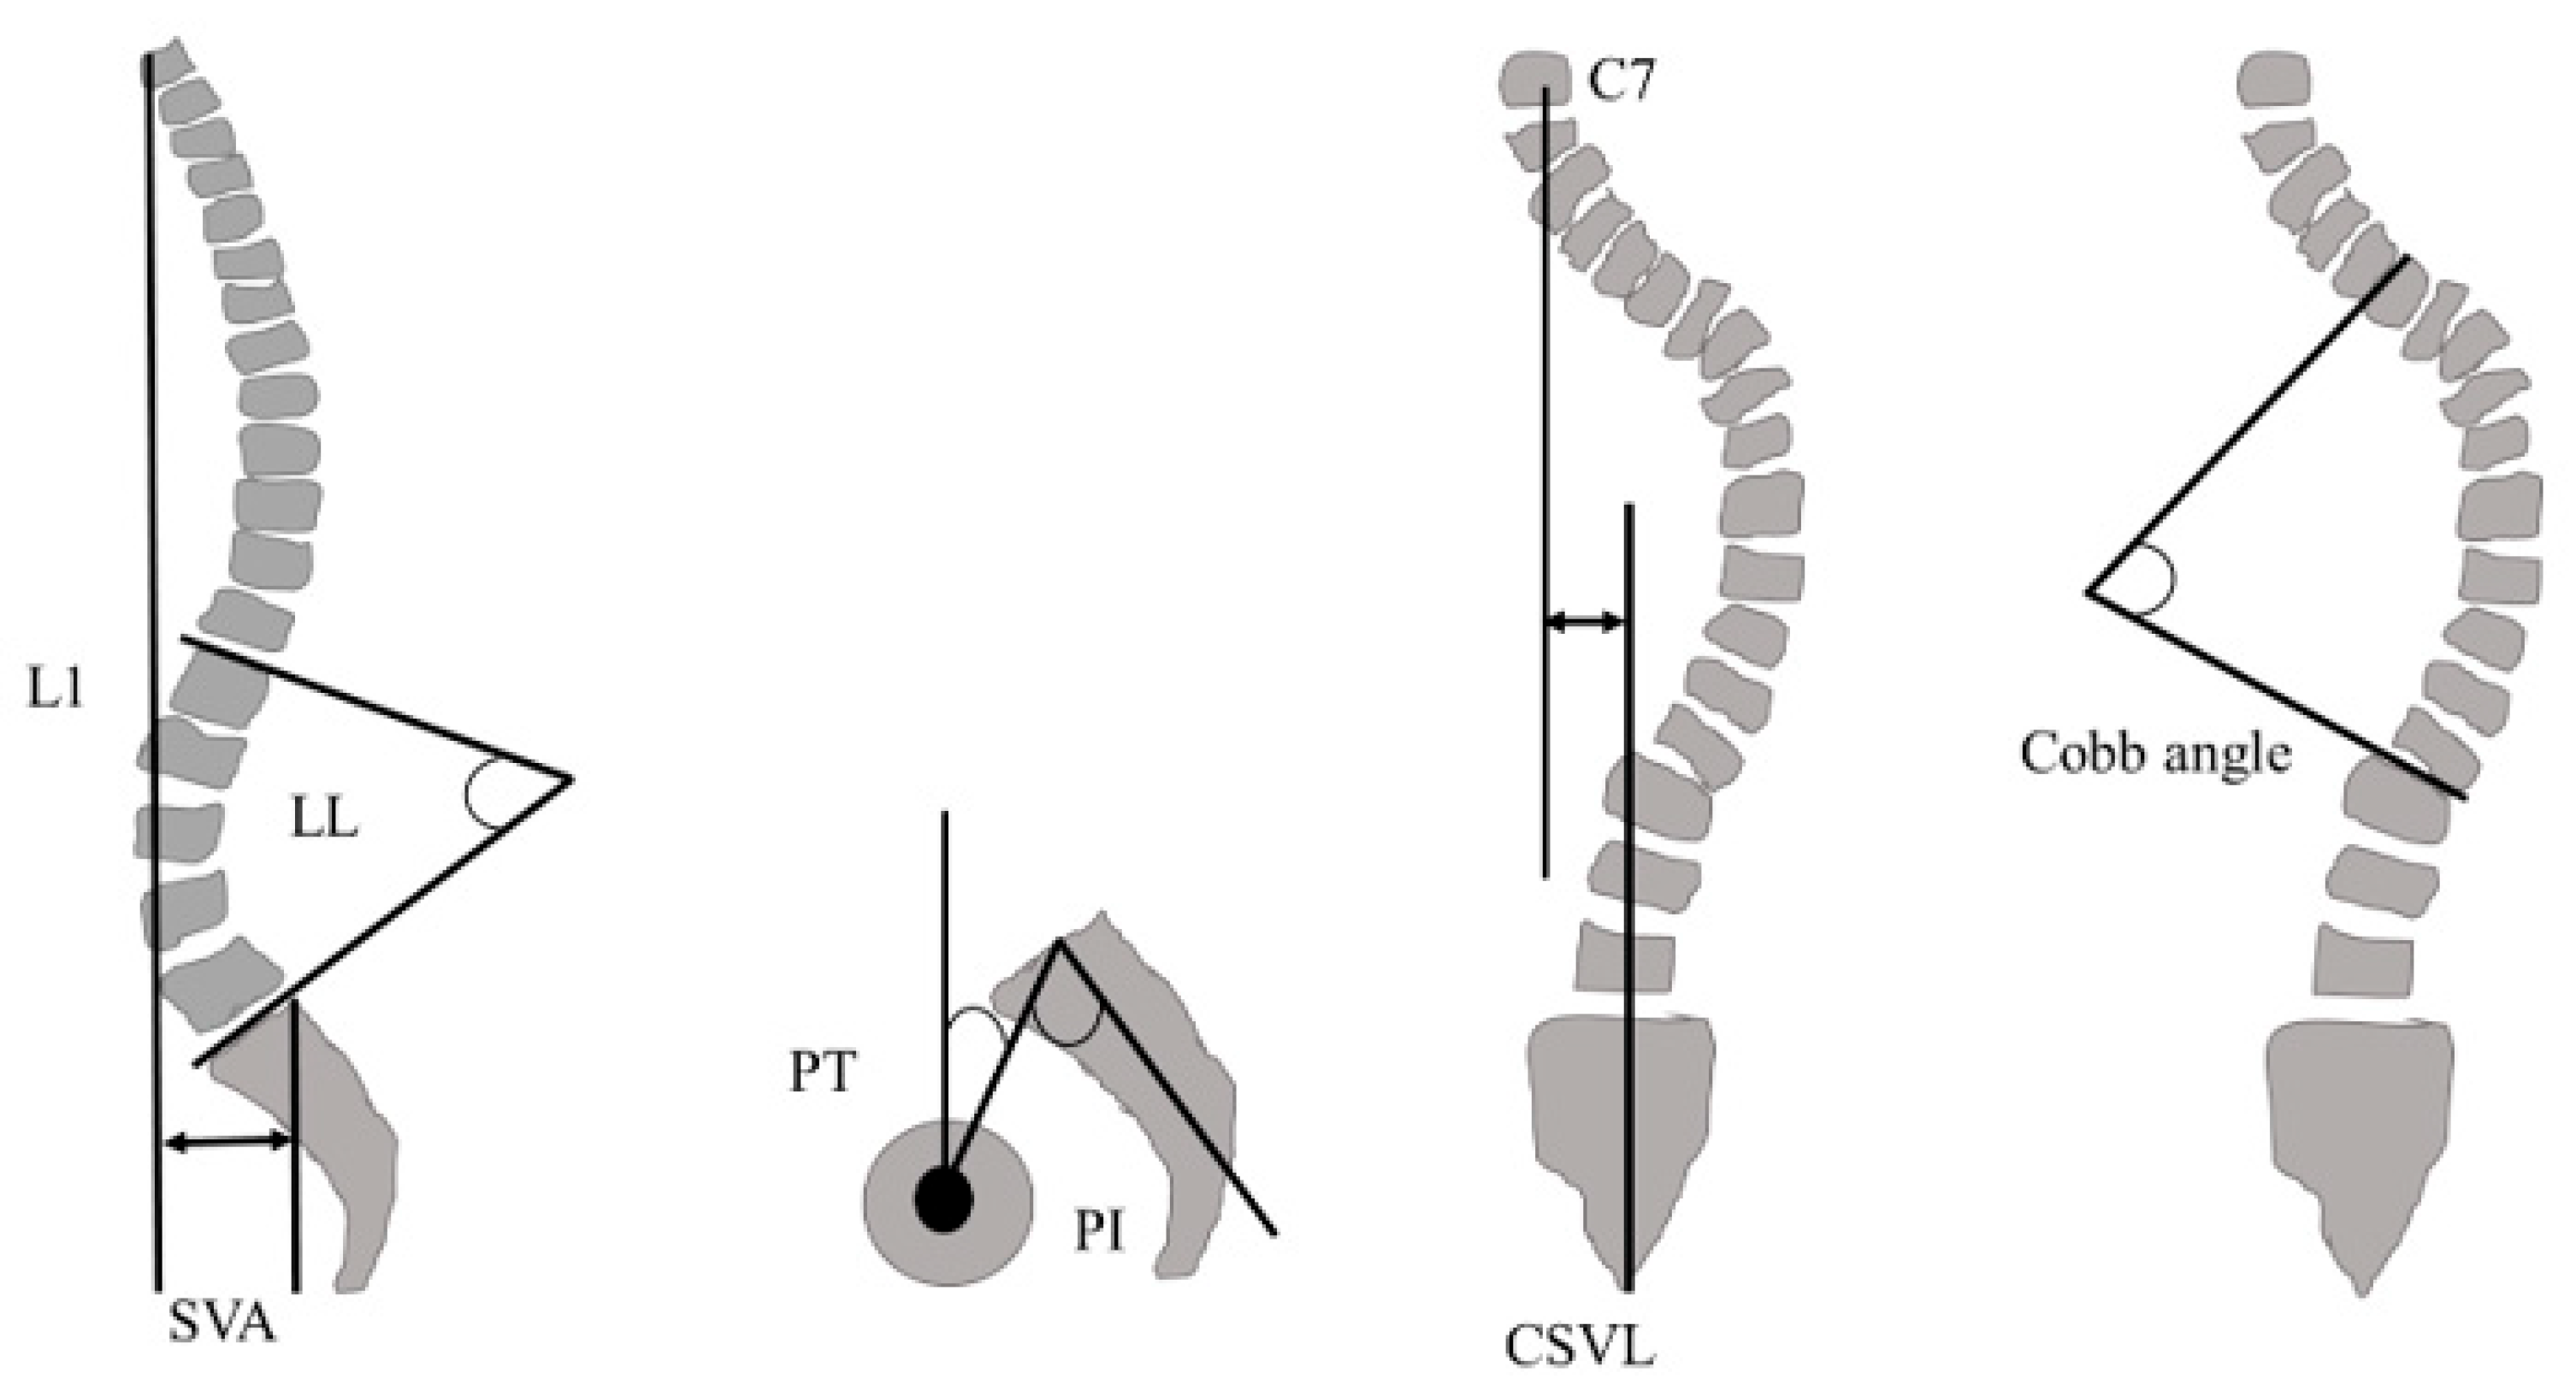

2.5. Spinopelvic Parameters